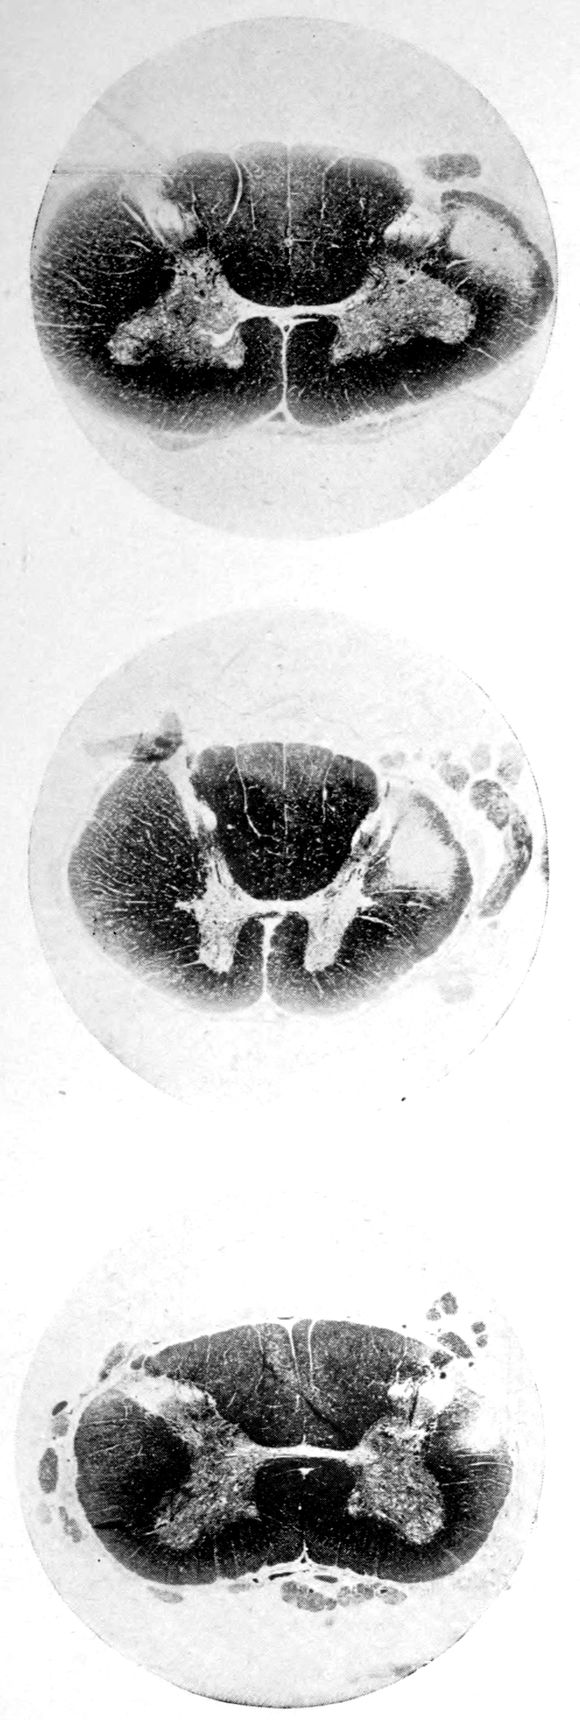

Case 4. (See previous figure for brain lesion.) Three levels of the spinal cord showing unilateral pyramidal tract sclerosis, 10 years after cerebral thrombosis.